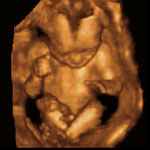

second trimester sonogram

“Any procedure at this stage is pretty gruesome. When I did second-trimester abortions, I did them late in the day, and when I’d get home, my wife would say, ‘You did one today, didn’t you?’ It would be all over my face.”